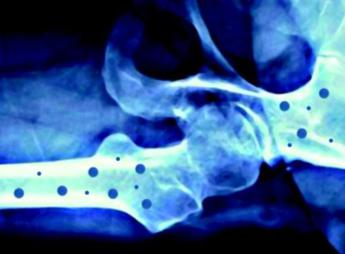

L’iniziativa ha il supporto incondizionato di Ibsa Farmaceutici Italia come main sponsor, e di Gedeon Richter, Organon, Accord Healthcare Italia, Ucb e Theramex come silver sponsor. Sono le aziende farmaceutiche che hanno scelto di sostenerne questi importanti progetti di informazione che, grazie a loro, possono essere portati avanti. L’osteoporosi – conclude la nota – è una malattia sistemica dell'apparato scheletrico, caratterizzata da una bassa densità minerale e dal deterioramento della micro-architettura del tessuto osseo, con conseguente aumento della fragilità ossea e del rischio di fratturarsi. —[email protected] (Web Info)